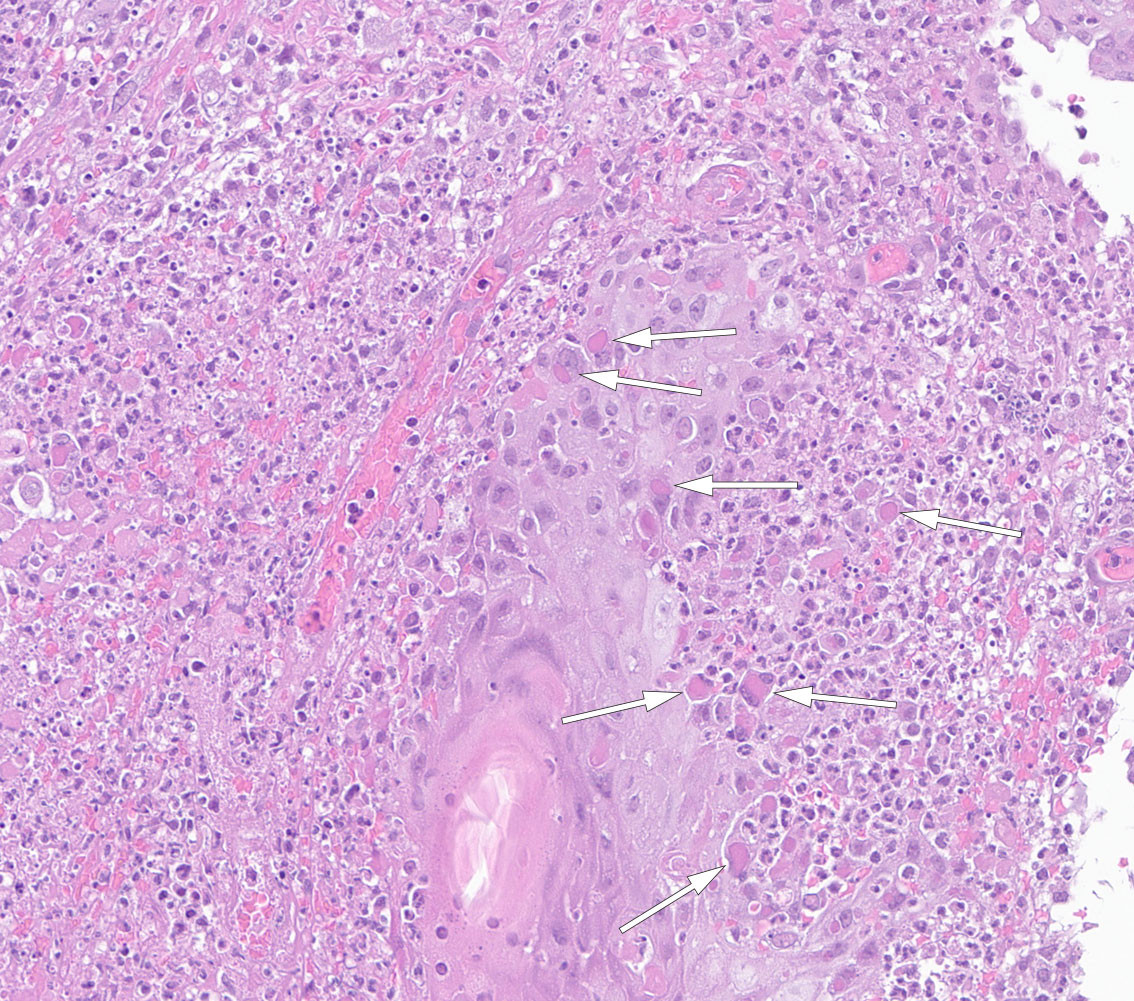

PCR for ortopoxvirus var positiv, mens spesifikk PCR for apekopper var negativ. Diagnostikk for videre differensiering innad i ortopoxgruppen er ikke tilgjengelig nasjonalt. Da det av akademiske årsaker var ønskelig med en bekreftelse av diagnosen, ble en ny penselprøve fra sårsekret sendt til Statens Serum Institut i Danmark for nærmere undersøkelse. Prøven ble her undersøkt med PCR og sekvensering, og kukopper ble bekreftet. Histologiske funn passet også med kukopper (figur 2). Leishmaniasis-DNA ble ikke påvist i hudbiopsi undersøkt ved referanselaboratoriet ved Oslo universitetssykehus.